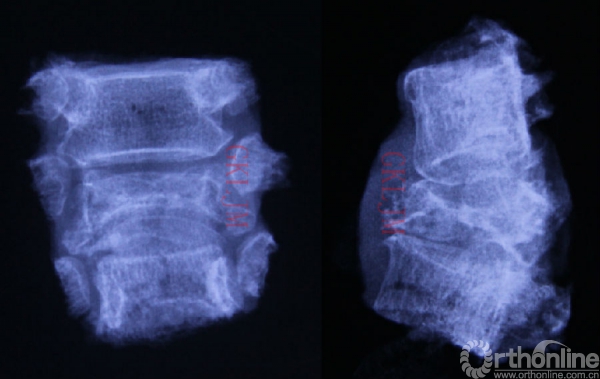

连同双侧肋椎关节整块切除的T1-3 X线正侧位平片,保证了肿瘤切除的安全边界